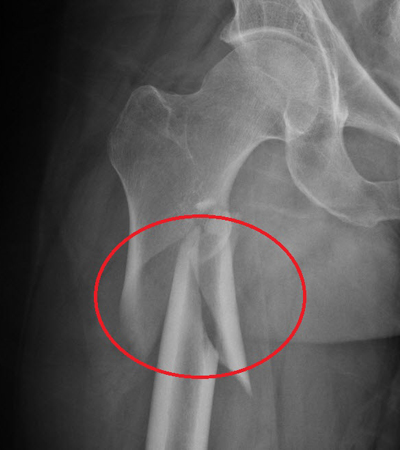

Η οστεοπόρωση είναι μια σιωπηρή νόσος, δεν παρουσιάζει συμπτώματα για μεγάλο χρονικό διάστημα. Αυτό σημαίνει ότι περνάνε αρκετά χρόνια, κατά τη διάρκεια των οποίων η οστεοπόρωση συνεχώς χειροτερεύει από πλευράς απώλειας οστικής μάζας και διαταραχής της μικροαρχιτεκτονικής δομής των οστών, μέχρι να εμφανιστεί το πρώτο της σύμπτωμα, που είναι το κάταγμα. Η οστεοπόρωση είναι νόσος όλων των οστών και γι’ αυτό κατάγματα μπορεί να συμβούν σε διάφορες θέσεις του σκελετού, αλλά συνήθως συμβαίνουν στους σπονδύλους, στον αυχένα του μηριαίου οστού και στο αντιβράχιο. Πιο συγκεκριμένα, περίπου 40% των οστεοπορωτικών καταγμάτων αφορούν τη σπονδυλική στήλη, 20% τον αυχένα του μηριαίου οστού, 20% το αντιβράχιο και 20% διάφορα άλλα οστά. Τα κατάγματα του αυχένα του μηριαίου οστού και του αντιβραχίου συμβαίνουν πάντοτε μετά από έναν χαμηλής βίας τραυματισμό, όπως είναι η πτώση από την όρθια θέση, ενώ συνοδεύονται πάντοτε από πόνο. Αντίθετα, τα σπονδυλικά κατάγματα συμβαίνουν συχνά χωρίς να προηγηθεί τραυματισμός και αρκετές φορές δεν συνοδεύονται από πόνο στη ράχη ή στη μέση παρά μονάχα από ένα ελαφρύ αίσθημα καύσου. Απώλεια ύψους και κύφωση αποτελούν όψιμες εκδηλώσεις της οστεοπόρωσης και οφείλονται σε σπονδυλικά κατάγματα.